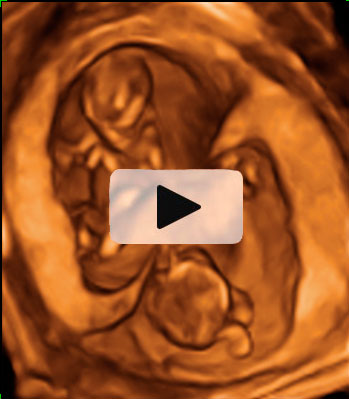

Aspecto de un bebé de 12 semanas tomado en ecografía 3D.

Se pueden apreciar con toda claridad la cabeza (aún más grande en proporción, que el resto del cuerpo), el tronco, las extremidades y el cordón umbilical. El niño ya se apoya con la espalda en el útero materno, lo que facilita la exploración por parte del ecografista.